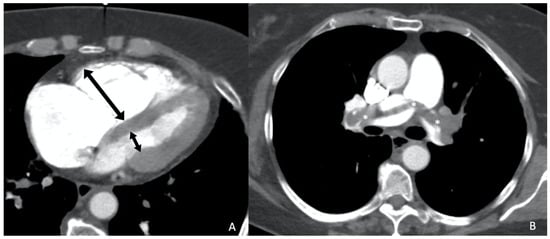

Further studies also underscore the importance of DECT [22,23,24,25,26]. As previously mentioned, these systems acquire data at two energy levels, enabling the differentiation of tissues with varying attenuation properties, which is especially beneficial for substances like calcium and iodine that exhibit high attenuation. The differentiated materials are visualized through their decomposition, and each material’s concentration can be calculated using an absorption algorithm. Different materials demonstrate distinct behaviors at various energy levels, allowing for more effective differentiation compared to single-energy spectrum imaging. This capability enables the creation of “iodine maps” (Figure 2), which specifically illustrate the presence of iodine in different slices. DECT can thus enhance the detection of pulmonary embolisms and aid in stratifying their severity [25]. On these maps, the distribution of iodine is directly proportional to the blood volume, allowing for the creation of pulmonary blood volume (PBV) maps. Defects distal to emboli are not commonly detected, as they occur more frequently (82–95%) in occlusive emboli compared to non-occlusive emboli (6–9%). Consequently, these defects are considered indicators of severity. Numerous studies have shown that a higher number and a larger size of defects in the PBV correlate with adverse outcomes, such as increased pulmonary arterial obstruction indices and RV dysfunction, which is assessed based on whether the patient has an RV/LV diameter ratio greater than 1 [25]. However, Im et al. [24] found that only the RV/LV ratio was a higher risk factor for all-cause mortality at 30 days, and not quantitative PBV measurement, in their propensity score matching comparing DECT with conventional CT. More recently, Lee et al. [23] published findings on the quantitative analysis of pulmonary perfusion, comparing the relative PBV values (%PBVs) and normalized PBVs (PBVms) among patients based on their pulmonary density, and discovered a significant correlation between the PBVm and sPESI.

Figure 2. Eighty-nine-year-old woman diagnosed with chronic pulmonary thromboembolism. (A) Axial CT angiography (maximum intensity projection—MIP—reconstruction) showing severe narrowing in the superior segmental artery of the left lower lobe (white arrow) as sequela of PE. (B) Fusion image of CT angiography and color-coded iodine density showing wedge-shaped perfusion defects (*) in the middle lobe, lingula, and left lower lobe, with the latter corresponding to the findings in image (A). (C) SPECT-CT fusion image showing wedge-shaped perfusion defects (*) similar to those obtained with dual-energy CT (B).